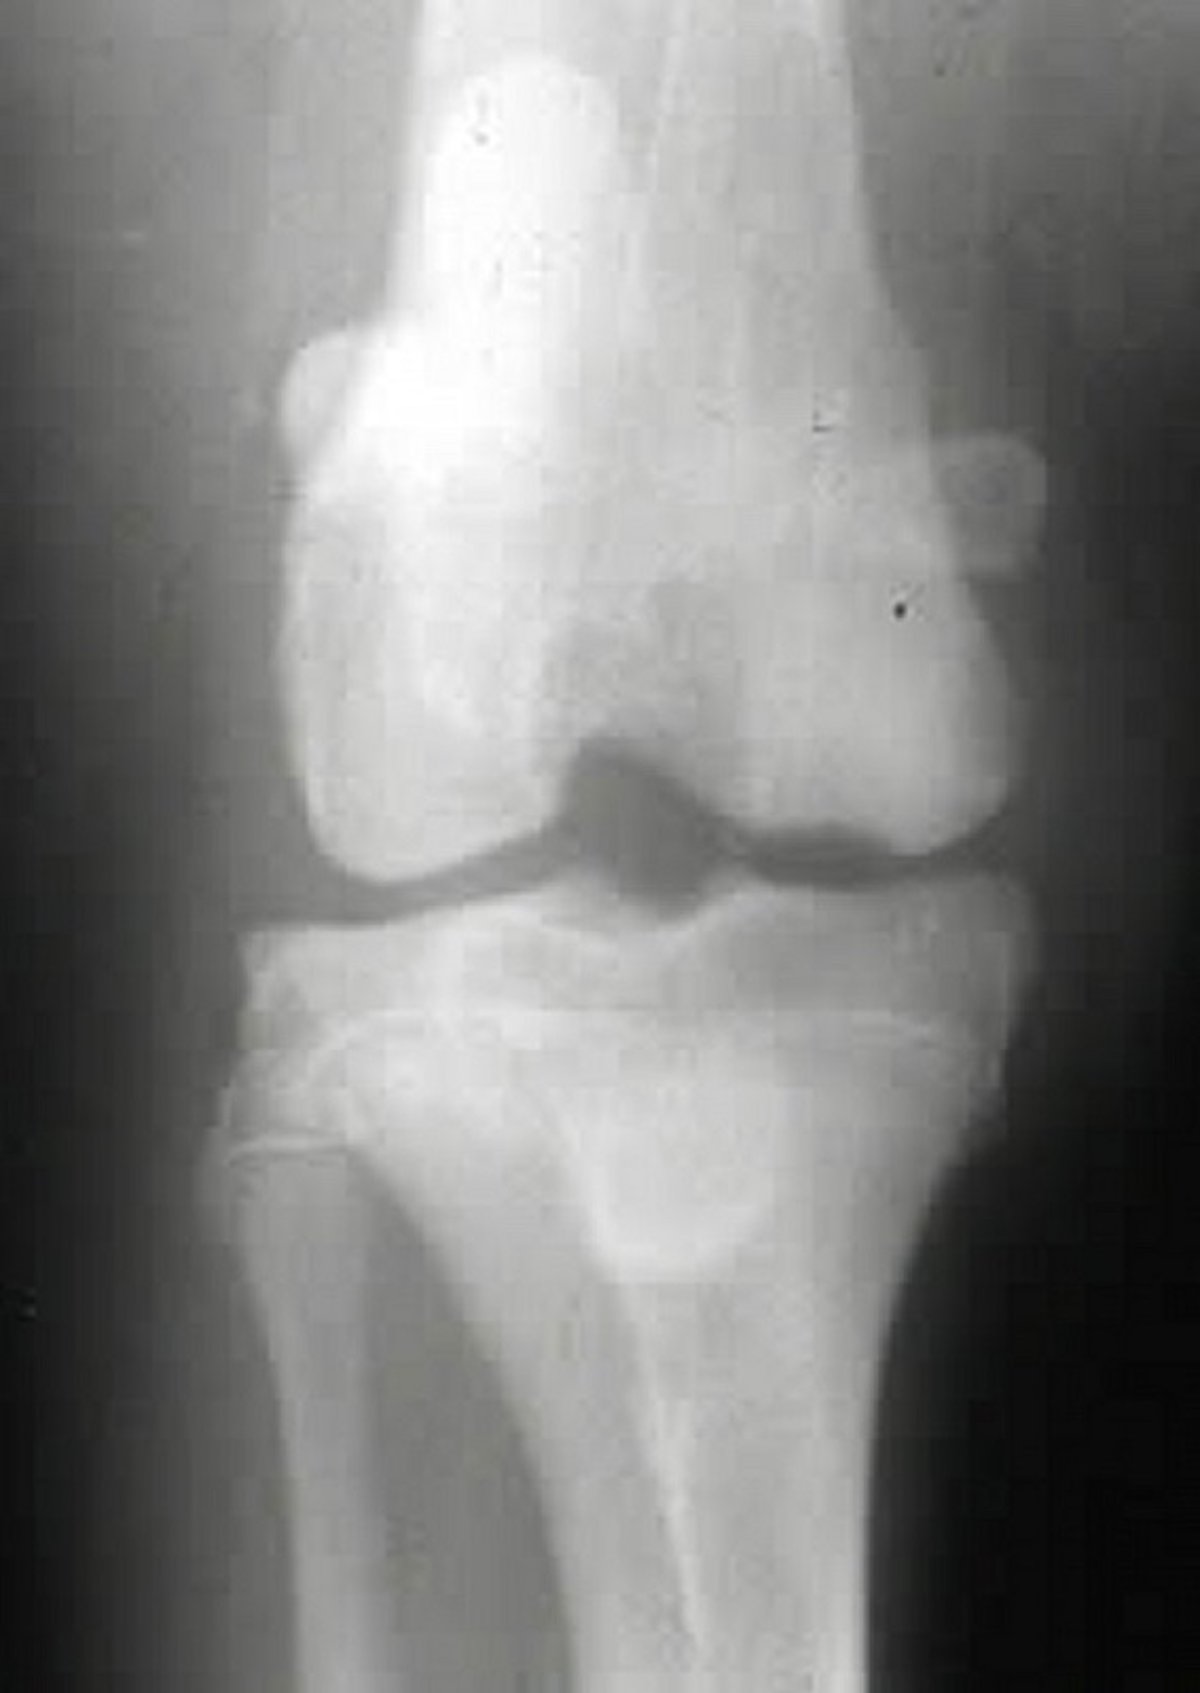

Craniocaudal radiographic view of the right stifle joint in a dog with osteochondrosis. Note the subchondral flattening of the medial femoral condyle.

Courtesy of Dr. Ronald Green.

Radiography is useful in identifying joint lesions associated with osteochondrosis; changes can include flattening of joint surfaces, subchondral bone lucency or sclerosis, osteophytosis, joint effusion, and joint mice (see and radiographs). Arthrography can be used to delineate cartilage flaps, and arthroscopy can also help to identify and guide the treatment of cartilage or joint lesions.